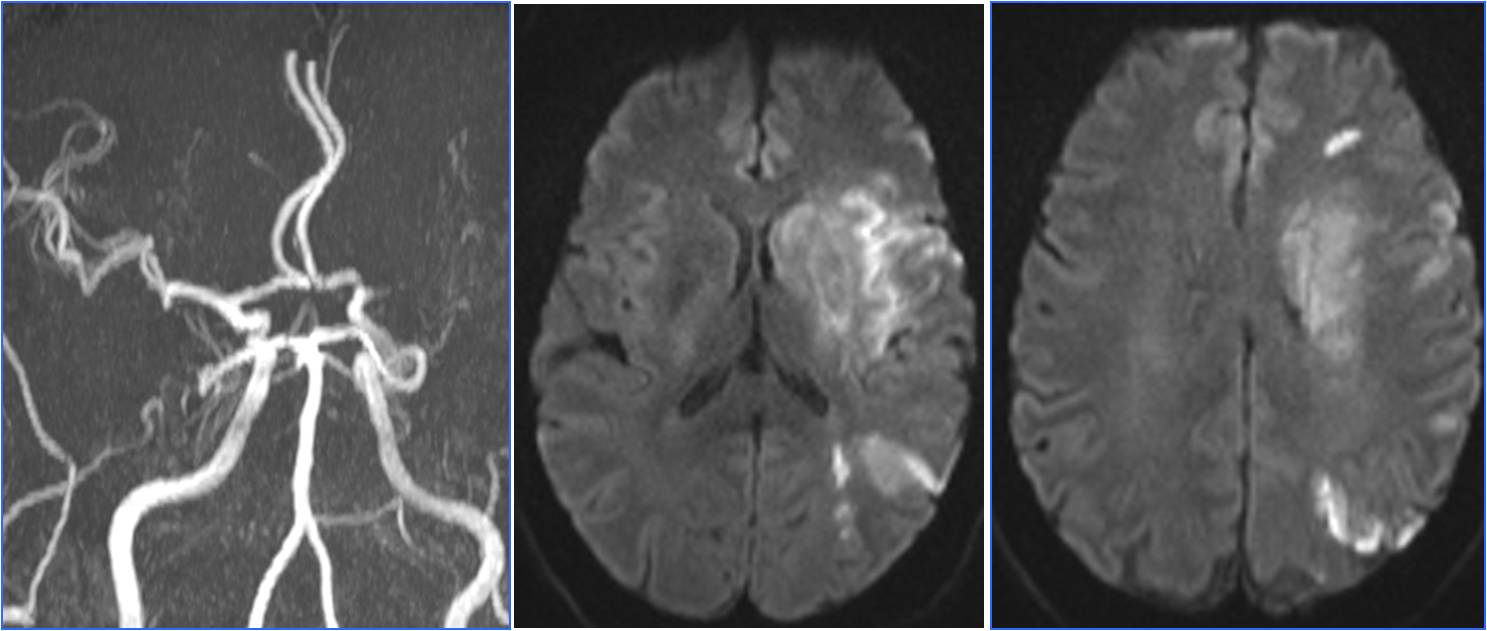

》昏迷后行头MRA检查。

▼7:22头CT

▼8:36头MRA

》急查血常规、凝血四项、肝肾电糖。

》签署静脉溶栓+动脉溶栓治疗知情同意书。

》8:54给予阿替普酶静脉溶栓,5mg静推,余45mg持续泵入。

》10:00股动脉穿刺。行气管插管全身麻醉。

▼于基底动脉远端及双侧大脑后动脉,分次给予阿替普酶共计5mg。

》12:10结束手术,带气管插管返回神经内科ICU。给予乌拉地尔持续泵入控制血压在110/70mmHg左右。

》第二天6:00出现中枢性高热,体温40℃。3天后转入普通病房。

》20天后出院,NIHSS评分5分。

▼溶栓后MRI